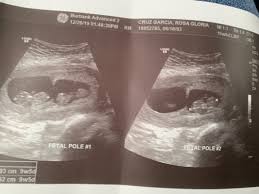

Ultrasonido De